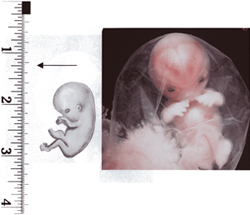

1.-2. týden těhotenství

Vajíčko ve vejcovodu čeká zhruba 12 až 24 hodin na příchod spermií. V ejakulátu je v průměru 250 milionů spermií, z toho pouze zhruba 400 se dostane až k vajíčku ve vejcovodu, přičemž cesta z pochvy do vejcovodu trvá spermiím až 10 hodin. Obvykle pouze jedna spermie uspěje a pronikne po zhruba 20 minutách snahy do vajíčka. Tím dojde ke vzniku oplodněného vajíčka, tzv. zygoty. V příštích 10 až 30 hodinách dochází ke splynutí genetických informací vajíčka a spermie. Pohlaví dítěte je určeno již v této chvíli – pokud spermie nese chromozom Y, narodí se chlapec, pokud chromozom X, narodí se dívka.

některé obrázky čerpány z http://mimiblog.cz/kt/tyden/1